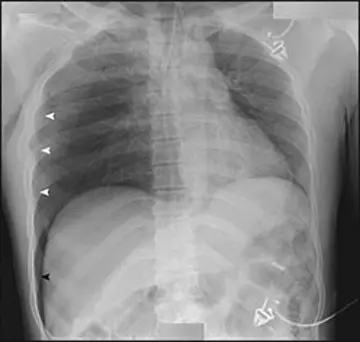

ترمیم خود‌به‌خود مهره مسطح

یک دختر3 ساله باسابقه‌ی سه هفته‌یی کمردرد مراجعه کرد.